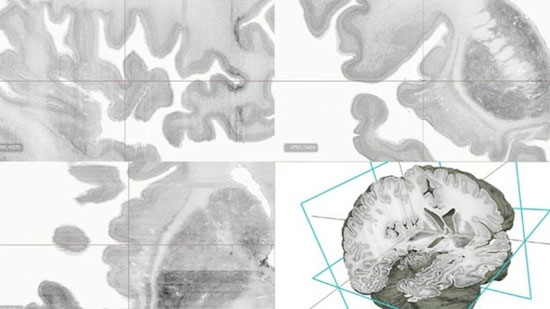

Các nhà khoa học vừa tạo ra mô hình kỹ thuật số 3D bộ não người có độ phân giải cao, được gọi là “Big Brain”.

Để thực hiện mô hình trên, các nhà nghiên cứu phải cắt mẫu não ra 7.400 lát cắt, với 80 tỷ tế bào thần kinh và mất 10 năm hoàn thành. Nhóm nghiên cứu phải nhuộm từng lát cắt để hiện rõ các chi tiết giải phẫu học và sau đó quét chúng vào một máy tính có độ phân giải cao. Bước cuối cùng, lấp ghép toàn bộ lại và quét vào máy tính.

Mô hình bộ não 3D đầu tiên trên thế giới - (Ảnh: BBC News)

Mô hình này cho phép các nhà giải phẫu học quan sát rõ từng chi tiết nhỏ nhất, thậm chí chi tiết đó nhỏ hơn cả sợi tóc. Với Big Brain, các nhà khoa học có thể nghiên cứu từ các lớp riêng biệt của vỏ não đến những tế bào của nó.

Giáo sư Katrin Amunts từ Trung tâm Nghiên cứu Julich, Đức, nhận định: “Ở những mô hình não trước đây, giống như việc sử dụng Google Earth, bạn có thể xem chi tiết, nhưng không thấy rõ so với mô hình 3D này".